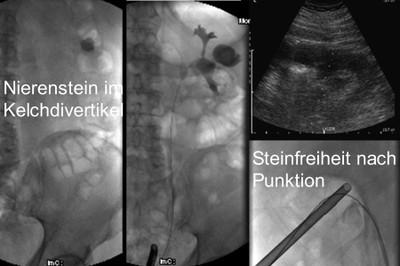

Die perkutane Nephrolitholapaxie lebt von der technischen Ausstattung und der Erfahrung der Operateure. Nur so können optimale Ergebnisse und niedrige Komplikationsraten erreicht werden. Unter Ultraschallkontrolle und digitaler Röntgentechnik wird der Nierenstein von aussen durch die Haut punktiert und dann unter videoendoskopischer Sicht zunächst mit Laser zerkleinert und dann abgesaugt.

Die zerkleinerten Teile werden herausgespült, abgesaugt oder mit einer Steinzange und Körbchenschlinge entfernt. Durch Röntgendurchleuchtung lässt sich dieses Vorgehen kontrollieren und die Niere auf weitgehende Steinfreiheit überprüfen. Nach dem Eingriff wird vorübergehend ein Nierenfistelkatheter in das Hohlsystem eingeführt, an der Haut fixiert, und der Urin in einen Sammelbeutel abgeleitet.